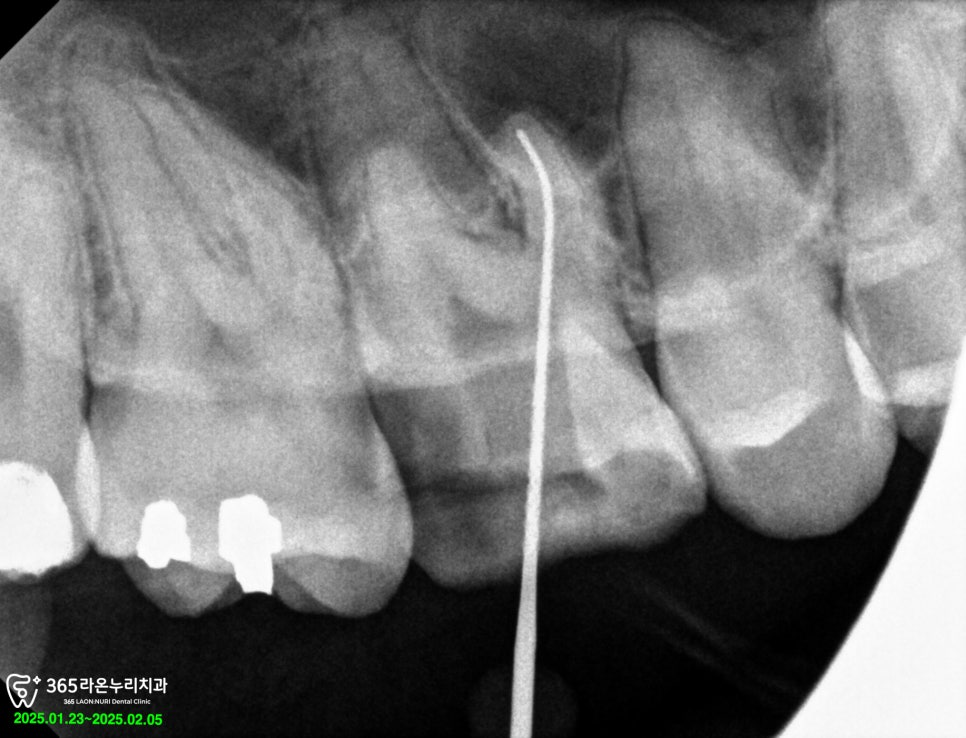

그다음 내부에 감염된 신경들을

제거해어 소독을 진행하였습니다.

내부를 소독한 다음 오래

유지할 수 있도록 신경관 내부를

깔끔하게 채워드렸습니다.

이후 소독을 진행하고

근관을 채운 다음 밀폐합니다.

보통 제1대구치라고 불리는 큰 어금니의 경우

신경 근관이 3개 또는 4개를 가지고 있습니다.

이분은 4근관으로, 다른 곳보다

치아의 뿌리가 더 많고

양이 일정하지 않기에

놓치기 쉬운 형태였는데요.